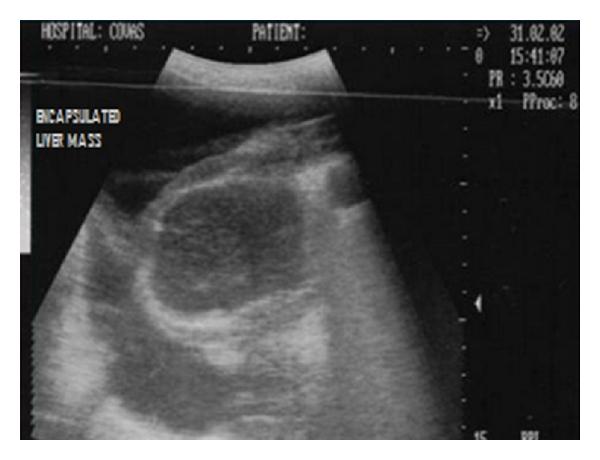

Hepatic disease is often treatable and has a predictable prognosis when a definitive diagnosis is made. The aim of clinicopathological evaluation of hepatobiliary affections is to identify and characterize hepatic damage and dysfunction, identify possible primary causes of secondary liver disease, differentiate causes of icterus, evaluate potential anaesthetic risks, assess prognosis and response to xenobiotics, and monitor response to therapy. This paper describes the different diagnostic methods and imaging techniques employed in diagnosis of hepatobiliary affections in dogs. Besides reviewing the significant clinical manifestations and imaging structural abnormalities in diagnostic approach to different hepatic affections, it also depicts radiographic, ultrasonographic, and wherever applicable, the laparoscopic characterization of different hepatic affections and target lesions encountered in clinical cases presented in the Teaching Veterinary Clinical Complex, COVAS, Palampur in the year 2007-2008.

肝病通常是可治疗的,一旦做出明确诊断,其预后是可预测的。肝胆疾病临床病理评估的目的是识别和描述肝损伤及功能障碍,确定继发性肝病可能的主要病因,鉴别黄疸的病因,评估潜在的麻醉风险,评估预后及对外源化学物质的反应,并监测治疗反应。本文描述了用于诊断犬肝胆疾病的不同诊断方法和成像技术。除了回顾不同肝病诊断方法中的重要临床表现和成像结构异常外,还描述了2007 - 2008年在帕兰普尔兽医临床综合教学中心(COVAS)出现的临床病例中不同肝病及目标病变的放射学、超声学特征,以及在适用情况下的腹腔镜特征。